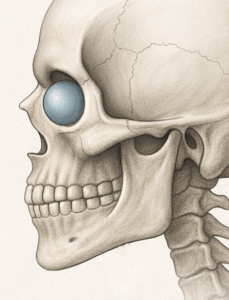

3D CT Findings in NOV

Vector Correction Strategy

Rather than simply adding volume, the implant is designed to reposition skeletal support:

- Converts a negative vector to neutral or slightly positive

- Advances the infraorbital support structure to match or exceed globe projection